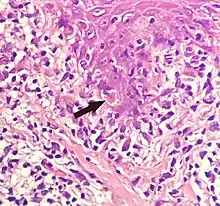

Civatte body

A Civatte body (named after the French dermatologist Achille Civatte, 1877–1956)[36] is a damaged basal keratinocyte that has undergone apoptosis, and consist largely of keratin intermediate filaments, and are almost invariably covered with immunoglobulins, mainly IgM.[37] Civatte bodies are characteristically found in skin lesions of various dermatoses, particularly lichen planus and discoid lupus erythematosus.[37] They may also be found in graft-versus-host disease, adverse drug reactions, inflammatory keratosis (such as lichenoid actinic keratosis and lichen planus-like keratosis), erythema multiforme, bullous pemphigoid, eczema, lichen planopilaris, febrile neutrophilic dermatosis, toxic epidermal necrolysis, herpes simplex and varicella zoster lesions, dermatitis herpetiformis, porphyria cutanea tarda, sarcoidosis, subcorneal pustular dermatosis, transient acantholytic dermatosis and epidermolytic hyperkeratosis.[37]